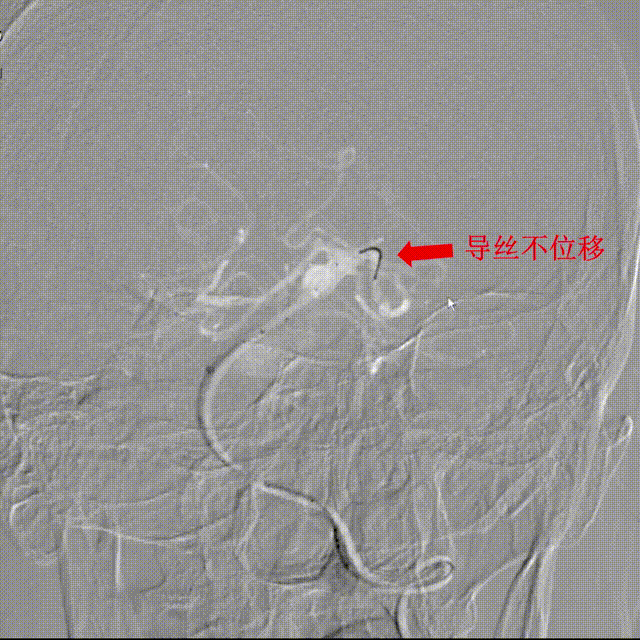

Lattice完全释放:

完全释放支架解脱。

造影显示整体打开贴壁良好。

3、Lattice头端导丝不前窜,降低了后循环释放时远端小血管破裂的风险,提升了后循环动脉瘤治疗的安全性。